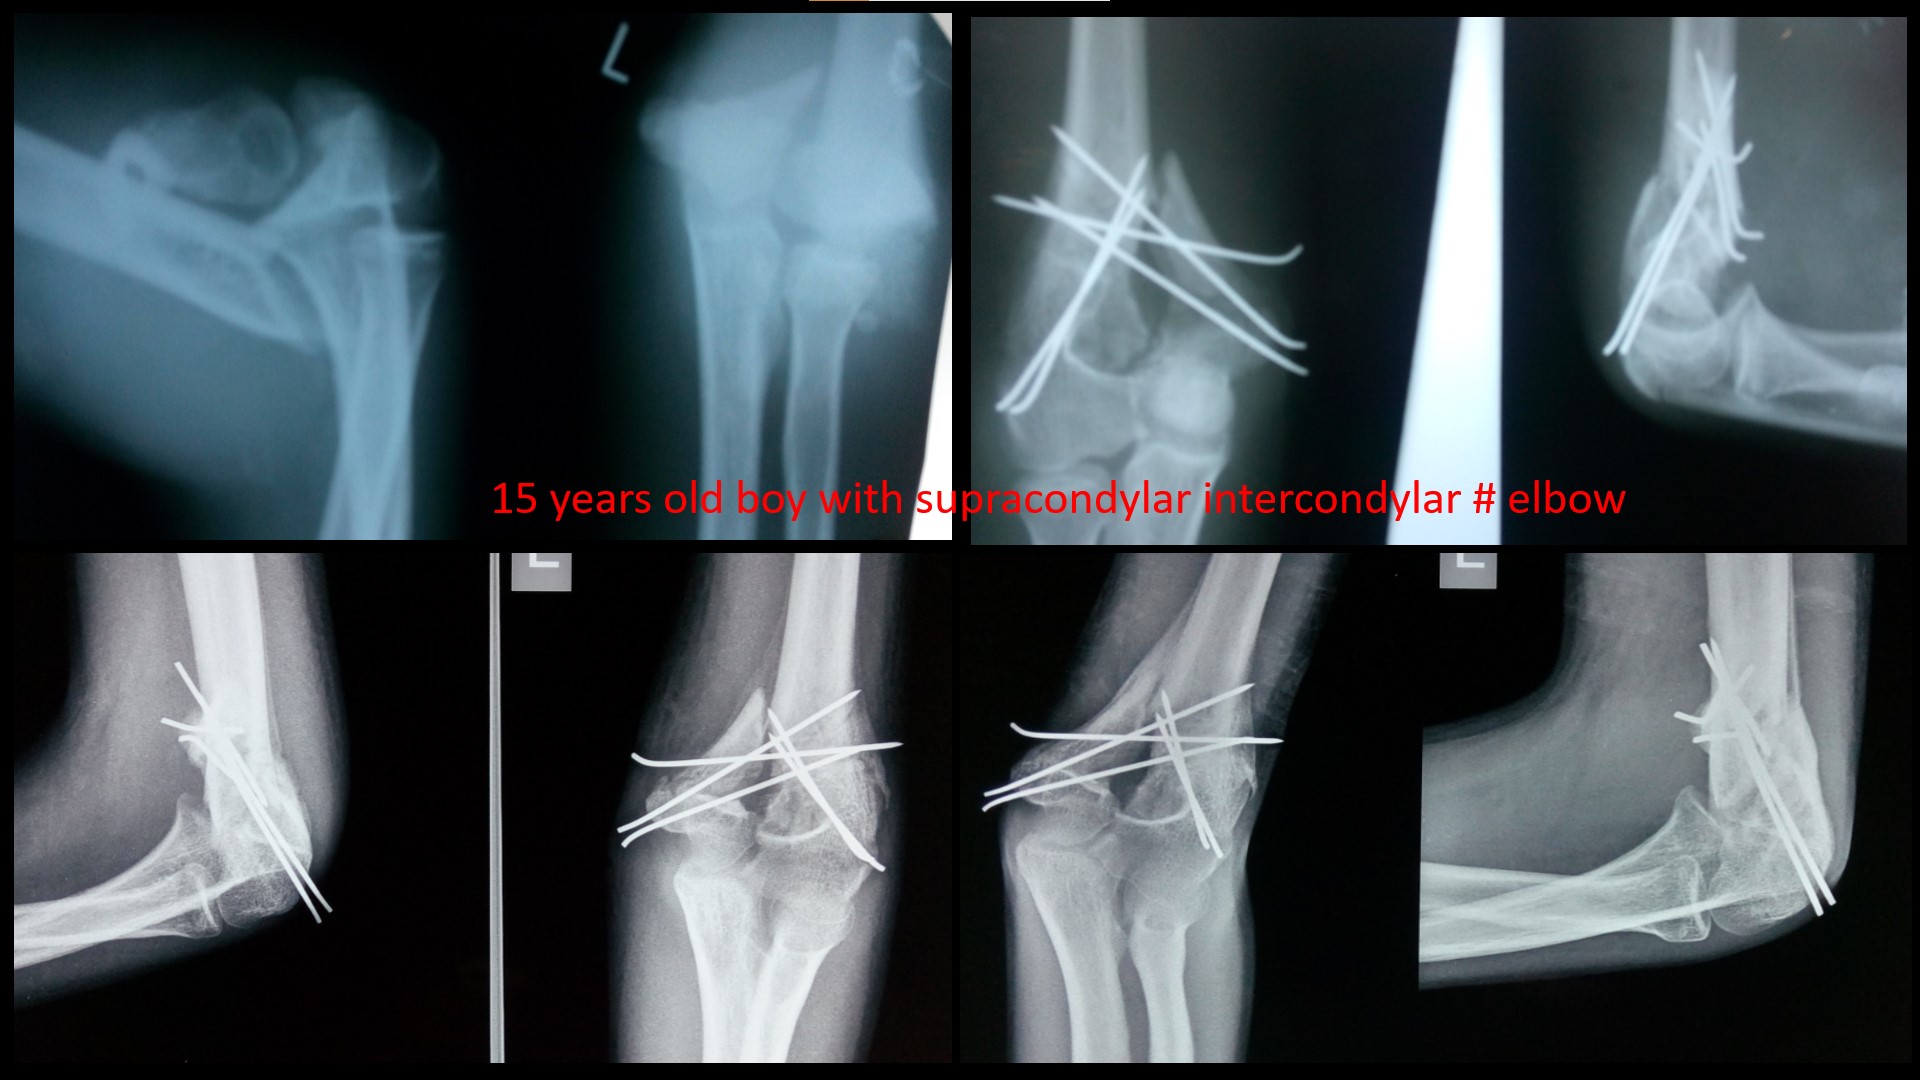

SUPRACONDYLAR #